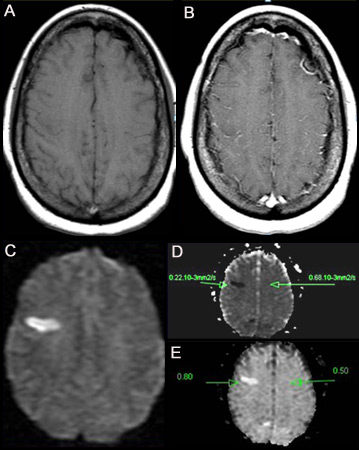

[Figure caption and citation for the preceding image starts]: (A) არაკონტრასტული T1-შეწონილი მრტ. (B) პოსტ-კონტრასტული T1-შეწონილი მრტ გვიჩვენებს ლეპტომენინგიალური სისხლძარღვების მინიმალურ გადიდებას მარჯვენა ფრონტალურ რეგიონში. (C) დიფუზურ-შეწონილი გამოსახულება (DWI), რომელიც წარმოგვიდგენს ჰიპერინტენსიურ უბანს მარჯვენა ფრონტალურ რეგიონში. (D) აშკარა დიფუზიის კოეფიციენტის (ADC) რუკაზე ჩანს ჰიპოინტენსიური კერა, რაც მიუთითებს შეზღუდულ დიფუზიაზე, რაც ურთიერთკავშირშია DWI მაღალ ინტენსიურობასთან და ექსპონენციურ დიფუზიასთან. (E) ADC მაჩვენებელი არის 0.22X10^-3mm^2/წამში, რაც შეესაბამება უმწვავეს ინფარქტს.ერიკ ე. სმიტის პერსონალური კოლექციიდან; გამოიყენება ნებართვით [Citation ends].